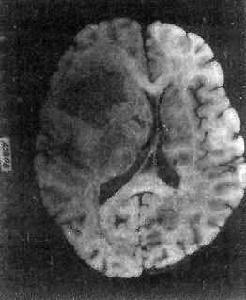

膠質母細胞瘤:腫瘤高度惡性生長快,病程短,自出現症狀至就診多數在3個月之內,高顱內壓症狀明顯,33%患者有癲癇發作,20%患者表現淡漠、痴呆、智力減退等精神症狀,(患者)可出現不同程度的偏癱,偏身感覺障礙、失語和偏盲等。